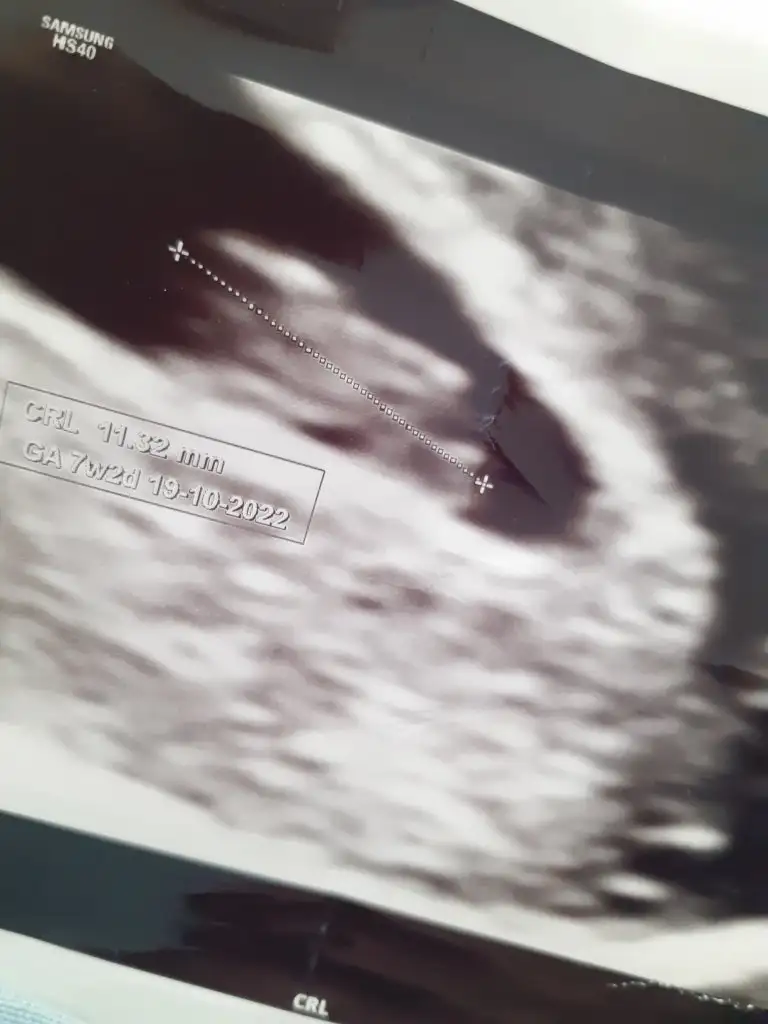

Bu var 7 haftalik karından başka da yokkuzum başka görüntün var mı? bence kız gibi ama yine de ayrıntıyla bi bakayım

kuzum burda çok daha net kız duruyorBu var 7 haftalik karından başka da yok